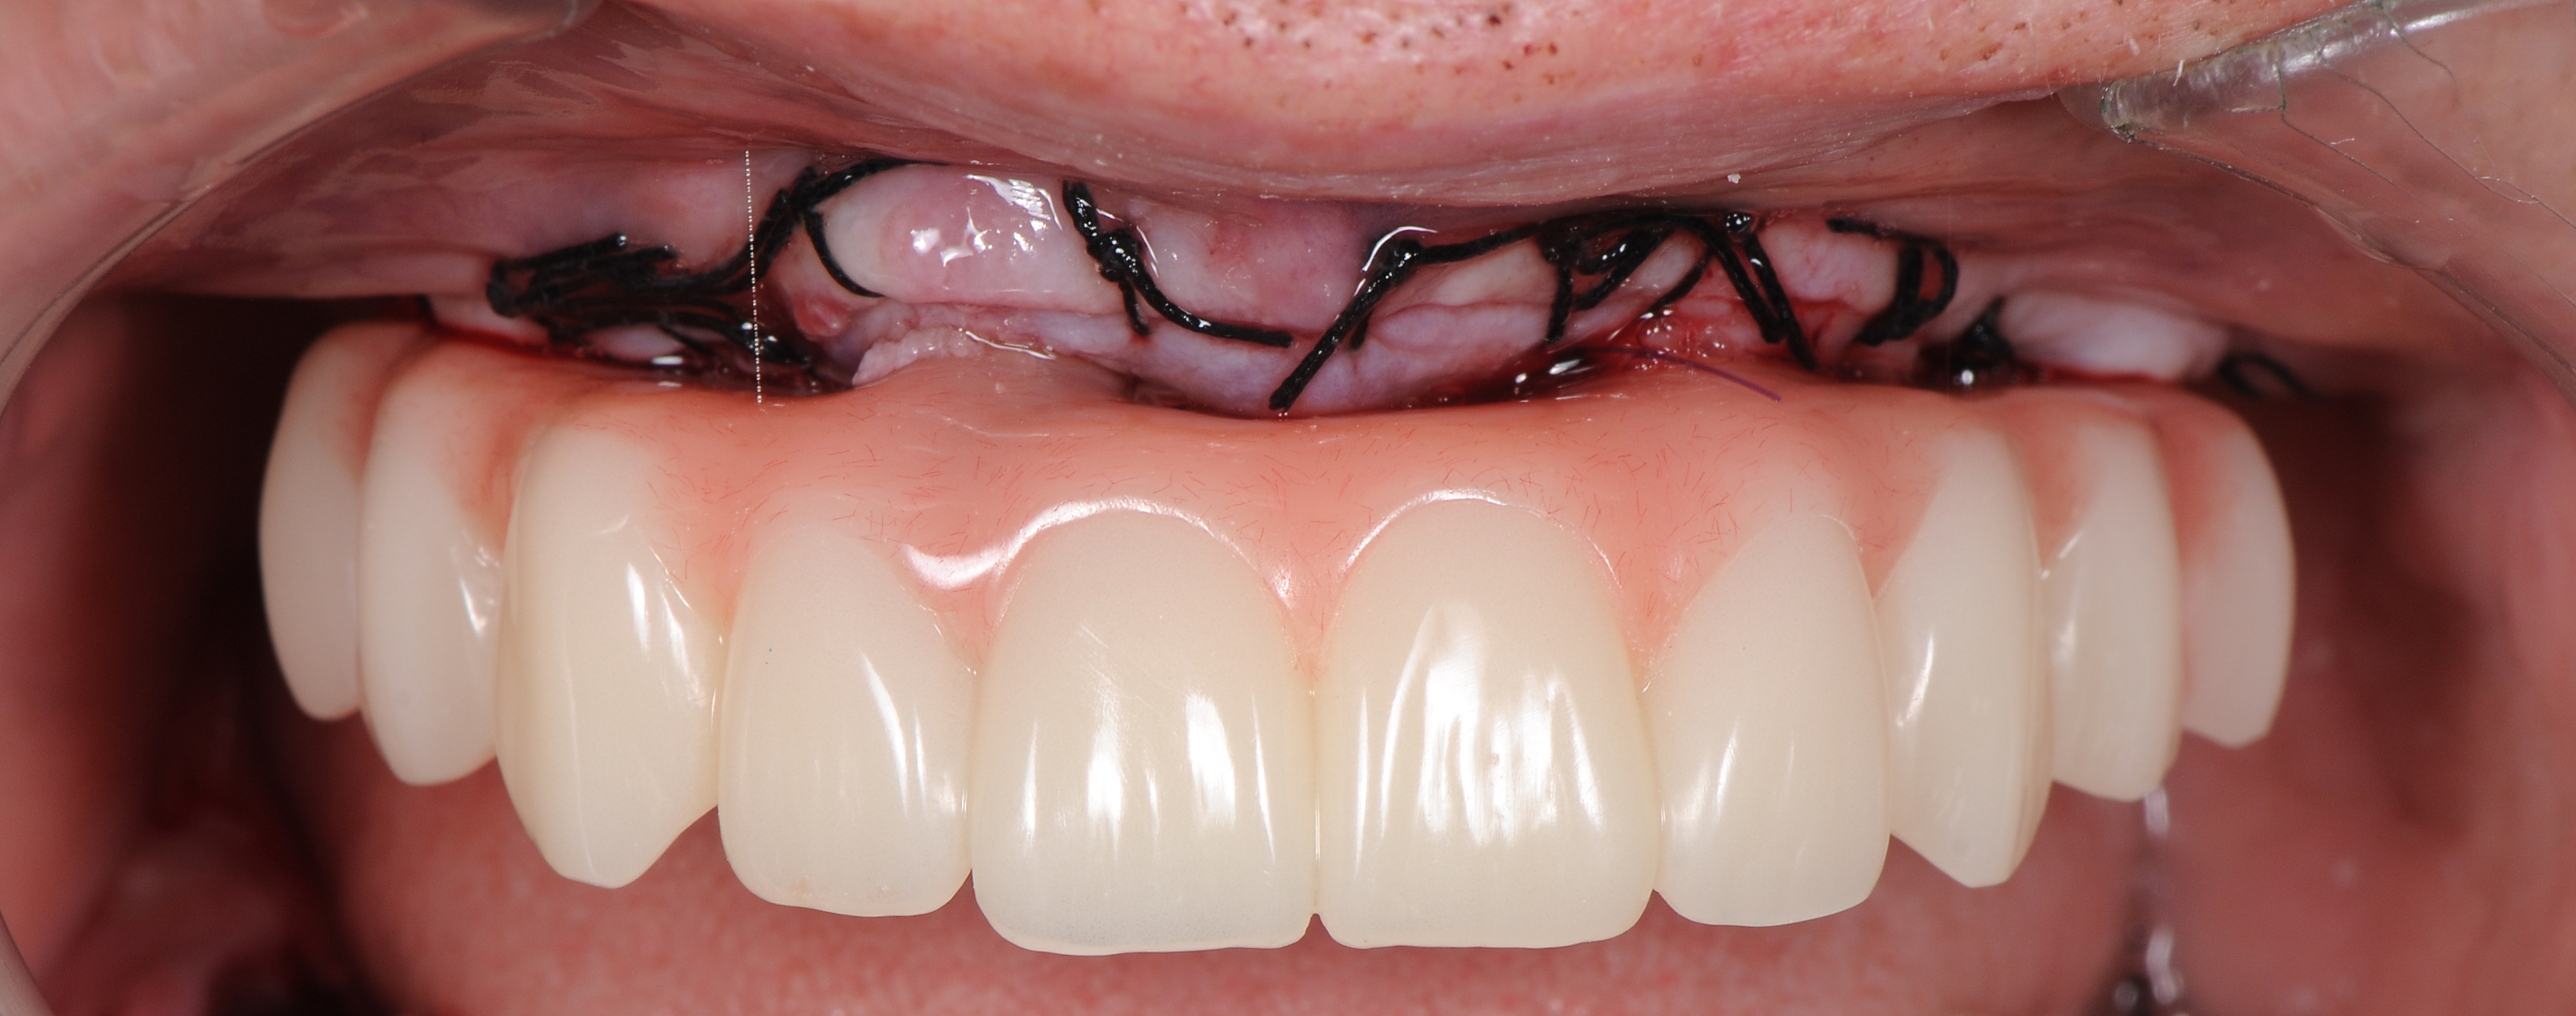

На «Multi – unit» абатменты зафиксированы пластиковые заживляющие колпачки. В небной части слизисто-надкостничного лоскута было сделано 2 перфорационных разреза в проекции фронтальных имплантатов, лоскут ротирован в вестибулярном направлении с расположением колпачков в зонах перфорации. Рана ушита шелковыми нитями без натяжения (рис 26,27,28).

Через 10 дней после имплантации пациент приглашен для контрольного осмотра и снятие швов (рис. 39).